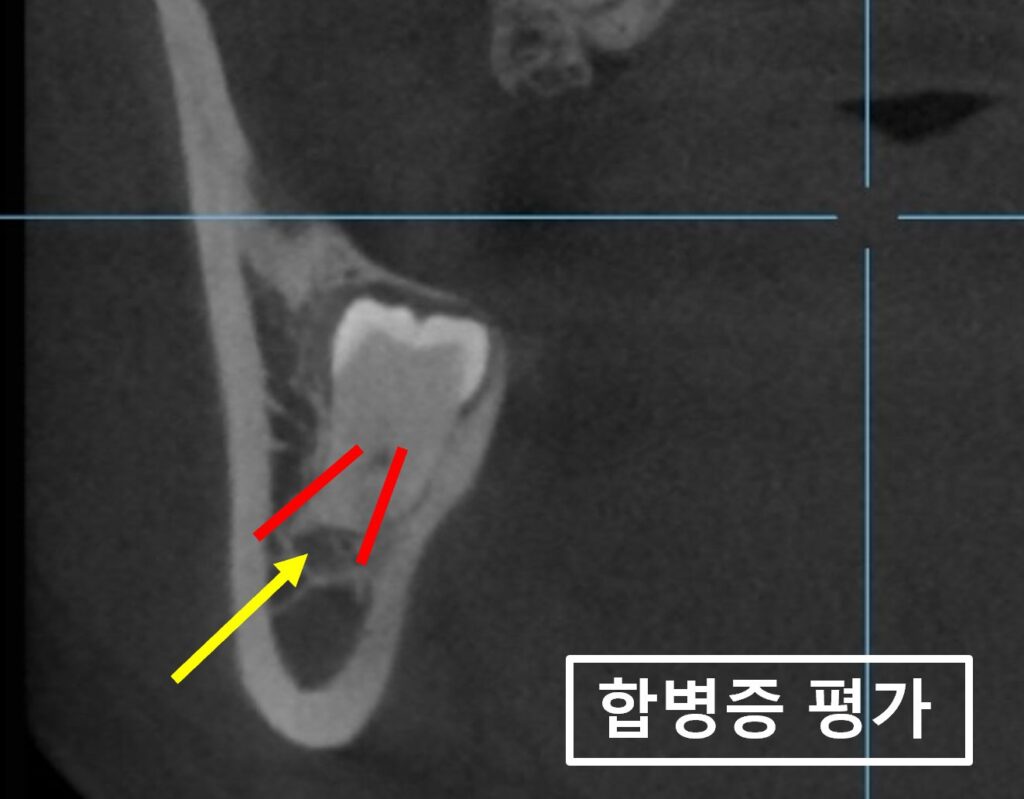

매교역치과 바른본에서 더 정확한 검사를 위해

촬영한 CT 사진입니다.

사랑니가 빨강색 화살표 방향으로 맹출을 하고 있고

이 방향이 앞쪽 어금니를 누르고 있는 것 같습니다.

환자분 연세가 사랑니 뿌리는 전부 자랐을 시기라

더 정확하게는

매복된 사랑니 주변 염증이

앞쪽 어금니를 압박하고 있다고 봐야 할 것 같네요.

아무래도 매복사랑니가

원인모를 치통의 이유인 것 같습니다.

사랑니발치를 위해서는 발치 후 나타날 수 있는

합병증을 미리 예측하고 설명해드려야 합니다.

노랑색화살표는 아래턱뼈신경으로

매복사랑니와 어느정도 거리가 있어

발치 후 이 신경이 놀랄 가능성은 적습니다.

하지만

매복사랑니의 뿌리 방향이 혀쪽을 향하고 있는데

빨강색점선이 가리키는 혀쪽 잇몸뼈가 얇고

사랑니뿌리 끝 일부는 이미 뼈가 녹아 없습니다.

매교역치과

이런경우

아래턱뼈신경보다는 정말 간혹이지만

설신경 손상 가능성이 있고

(Lingual nerve damage)

혀쪽 잇몸뼈의 골절 가능성도 있습니다.

(Lingual plate fracture)